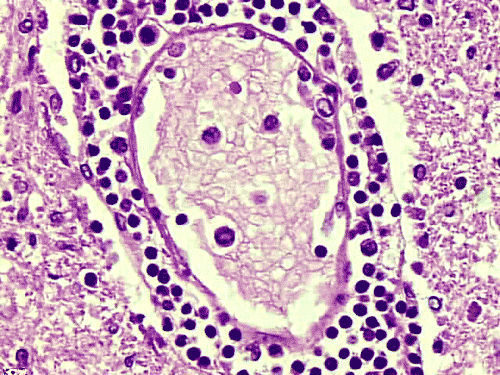

The overall tissue preservation is less than optimal because of postmortem autolysis. Panel A and B are taken from the cerebellum. The molecular layer, Purkinje cell layer, and internal granular layer are included (Panel A). Solitary eosinophilic intracytoplasmic inclusions of variable size are present in the Purkinje cells. No inflammatory cell infiltration is present in the cerebellum. The vacuolar spaces (Panel B) is partly due to autolysis and partly due to hypoxic/ischemic changes. Pyramidal cells in the hippocampus (Panel C), cortical neurons in parietal lobe (Panel D) and other neocortical areas adopted an elongated and contracted contour with loss of nuclear details. These are histologic features consistent with hypoxic/ischemic changes. Similar to the cerebellum, solitary eosinophilic cytoplasmic inclusion bodies are present and there is no inflammatory cell infiltration. Multiple eosinophilic cytoplasmic inclusion bodies within a single neuron are occasionally found. Some of these neurons containing multiple inclusions from the substantia nigra are illustrated in Panel E. Although inflammatory cell infiltration is scant in the cerebrum and cerebellum, perivascular chronic inflammatory cell infiltrations are common in the medulla (Panel F and G), in the paravertebral sympathetic ganglion (Panel H and I) and in the spinal cord (not shown). Intracytoplasmic inclusions, however, are not found in the medulla, spinal cord, and paravertebral sympathetic ganglion. Under the electron microscope, rod-shape or bullet-shaped viral particles are found (Panel J).

The brain and spinal cord may appear swollen but are usually free of focal lesions. Histopathologically, rabies is a widespread polioencephalomyelitis. Leptomeningeal and parenchymal perivascular lymphocytic infiltrations are usually present but often not intense. Neuronophagia can also be seen. The amount of inflammation of the case under discussion is, in fact, on the intense side of the scale. The pathognomonic Negri bodies 10, 11, 12 are sharply delineated, round to oval, eosinophilic, neuronal cytoplasmic inclusions; first described by Negri in 1903 10. These inclusions are often solitary but may also be multiple in a single neuron. Lyssa bodies refer to less well delineated and more pleomorphic neuronal cytoplasmic viral inclusions. Babes’ nodules refer to clusters of microglia that remain after destruction of neurons. When immunohistochemistry is employed, the distributions of viral antigen are far more extensive than that estimated by conventional light microscopy 13. Negri body and rabies viral antigen as demonstrated by immunohistochemistry are most commonly seen in large neurons of the hippocampus (Pyramidal cells), cerebellum (Purkinje cells), thalamus, basal ganglia, cerebral cortex and in the brain stem, especially gray matter of the pons and medulla. They are also found in spinal cord motor neurons and dorsal root ganglion, especially in the paralytic form.  Immunohistochemistry also demonstrated rabies viral antigen in astrocytes and oligodendrocytes 13. Characteristically, a striking discrepancy between the degree of inflammation and amount of inclusion bodies is observed, as in our case, in many cases.